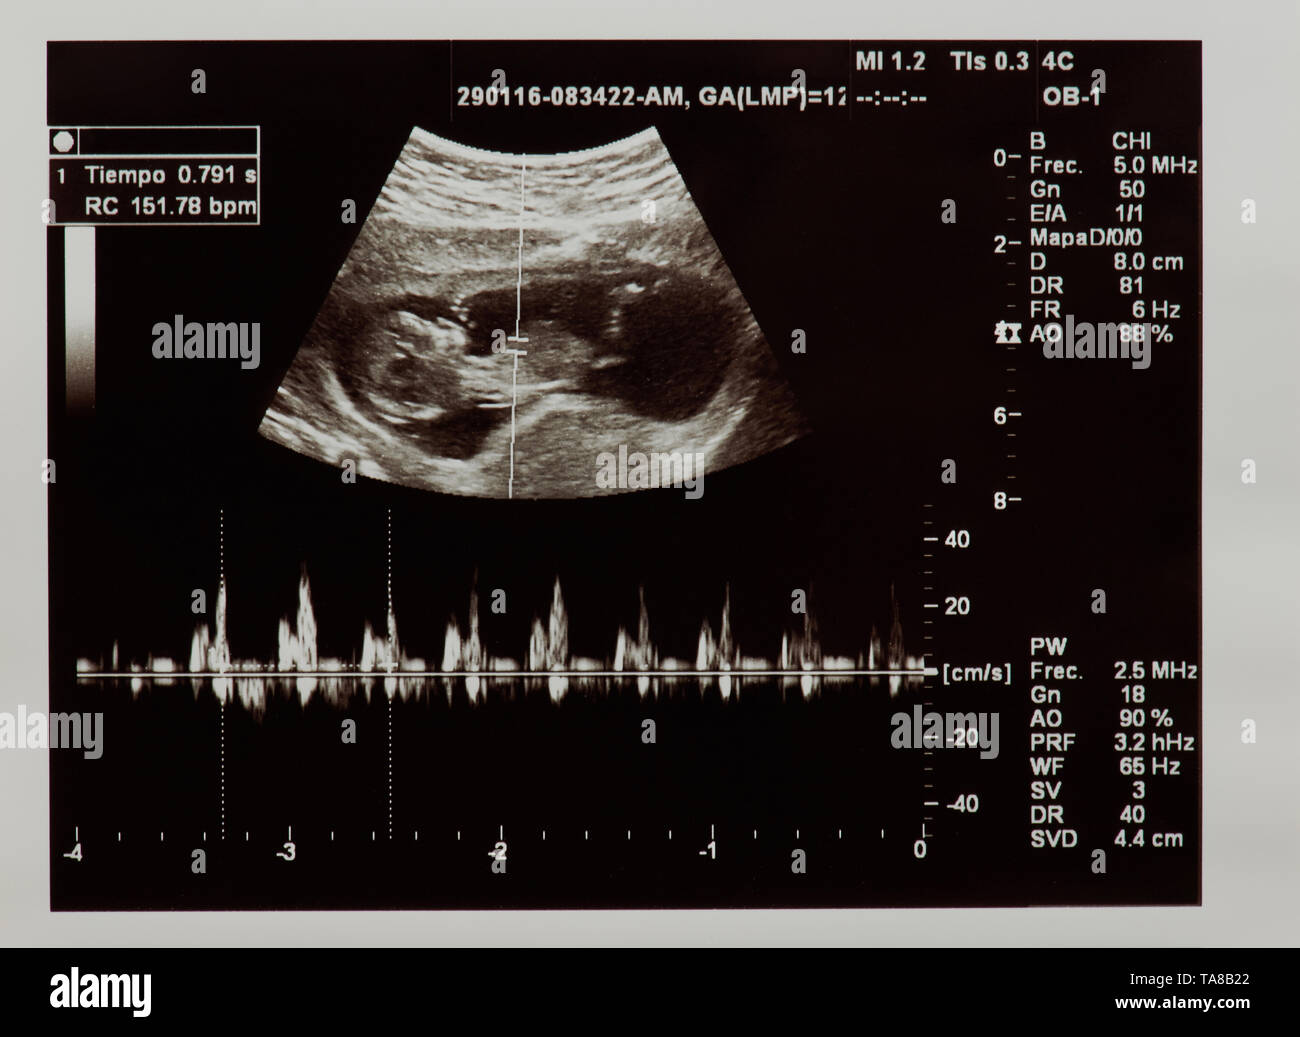

Ultrasound scan of future baby with heart beat parameters Stock Photohttps://www.alamy.com/image-license-details/?v=1https://www.alamy.com/ultrasound-scan-of-future-baby-with-heart-beat-parameters-image247276010.html

Ultrasound scan of future baby with heart beat parameters Stock Photohttps://www.alamy.com/image-license-details/?v=1https://www.alamy.com/ultrasound-scan-of-future-baby-with-heart-beat-parameters-image247276010.htmlRFTA8B22–Ultrasound scan of future baby with heart beat parameters